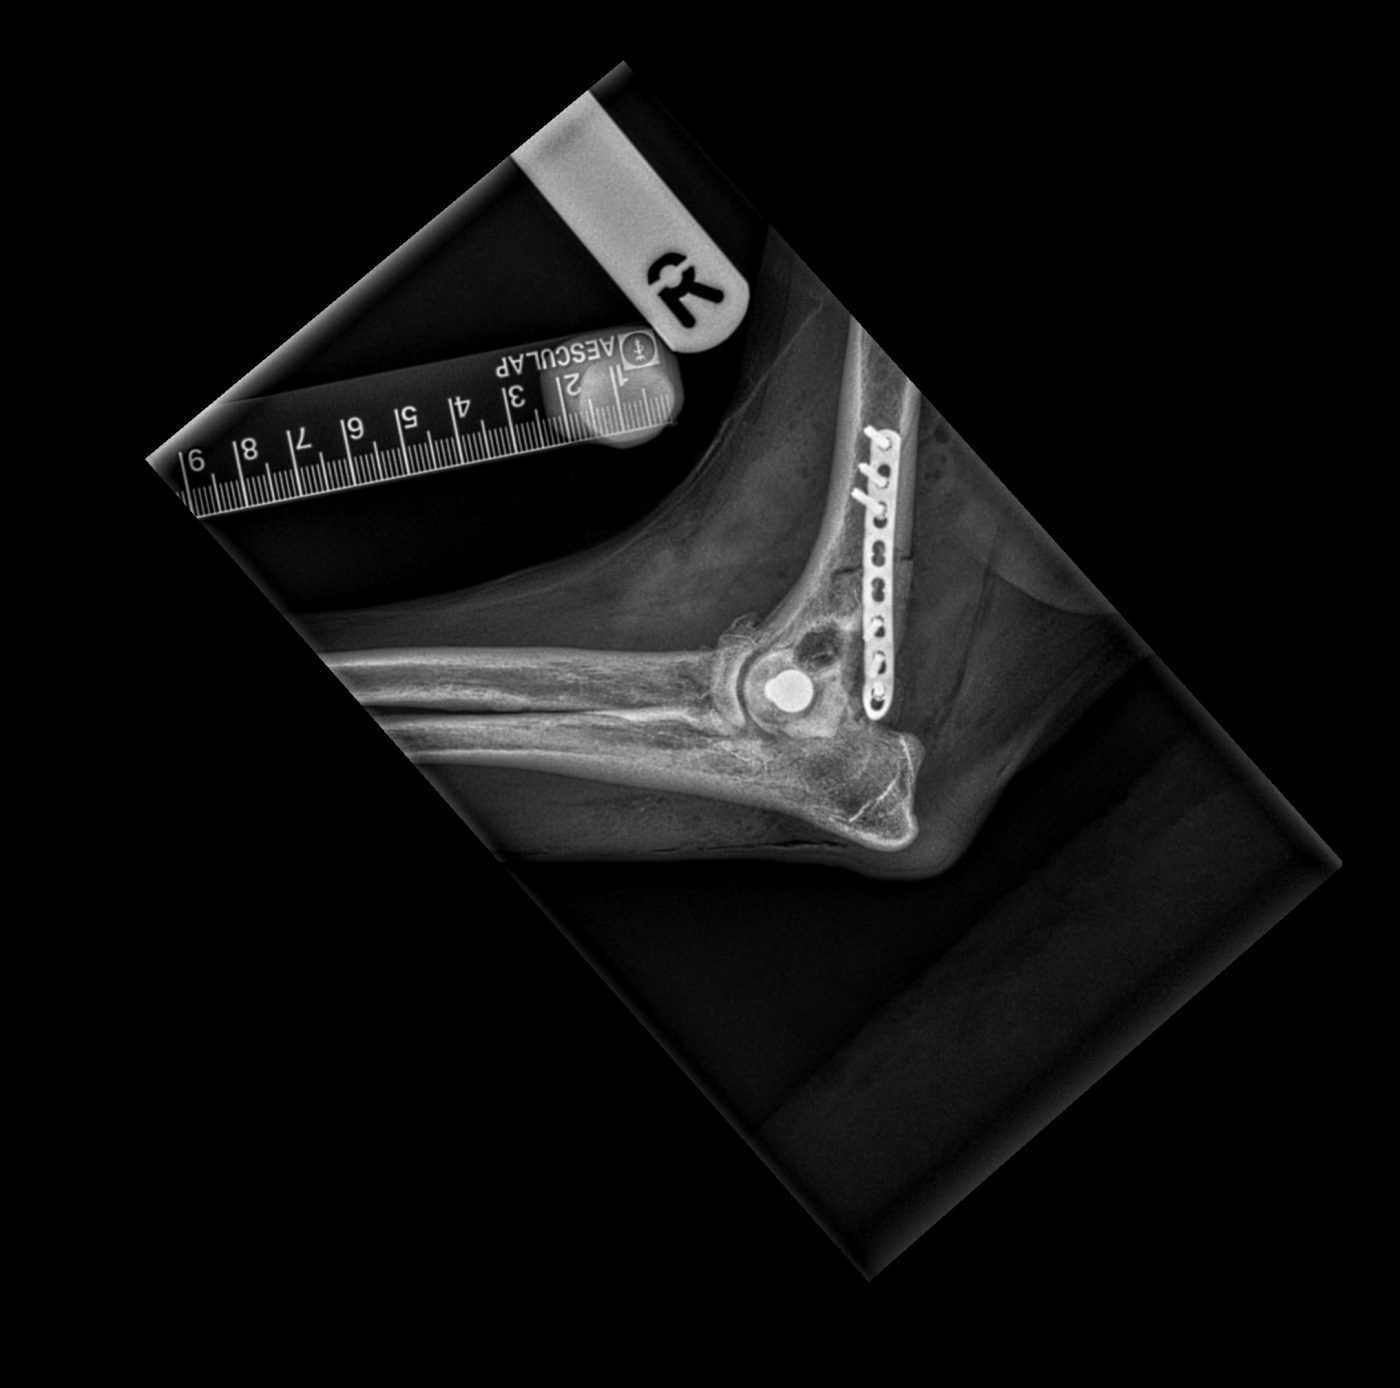

Surgical repair was required, and this was performed by practice principal Dr Martin Hobbs and senior veterinary surgeon Dr Rupert Davenport. A CT scan was carried out prior to the surgery to assist with pre-surgical planning. After incision, the fractured bone was manipulated back into a normal anatomical position, and secured in place using plates and screws. The site was closed using dissolvable sutures, and post-operative x-rays confirmed the surgery had been successful.

Chase recovered from the surgery well and he was hospitalised overnight for monitoring and pain relief. The very next day he had begun to gently place weight onto the leg and was discharged with instructions for strict cage rest and ice packing 3-4 times daily.